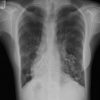

– Giãn phế quản (Bronchiectasis) là giãn không hồi phục một phần của cây phế quản và thường đi kèm với hiện tượng dày thành phế quản và ứ đọng chất nhầy. Có thể giãn ở phế quản lớn trong khi phế quản nhỏ vẫn bình thường hoặc giãn ở phế quản nhỏ trong khi phế quản lớn bình thường.

– Bình thường khẩu kính phế quản ngang với khẩu kính động mạch đi kèm. Trường hợp giãn phế quản, khẩu kính của phế quản sẽ lớn hơn động mạch đi kèm.